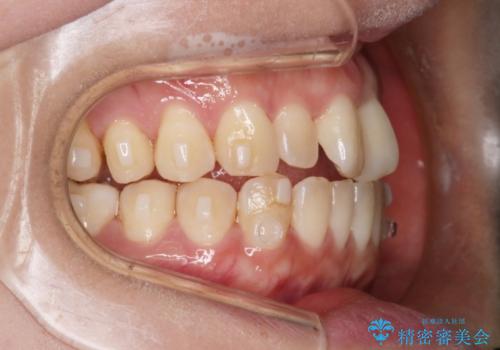

【インビザライン】前歯の捻れ気になる

- 上の前歯の捻れを主訴に来院されました。

前歯の捻れとがたつきを改善するために、IPR(歯と歯の間を削る処置)と歯列拡大をすることで歯並びを整えていく治療計画を立てました。

かみ合わせを整えるためにゴム掛けも行いながら、治療していきました。

患者様にマウスピースの使用とゴム掛けを頑張っていただいたおかげでリファイメント(マウスピースの再発注)も1回で終了することができました。